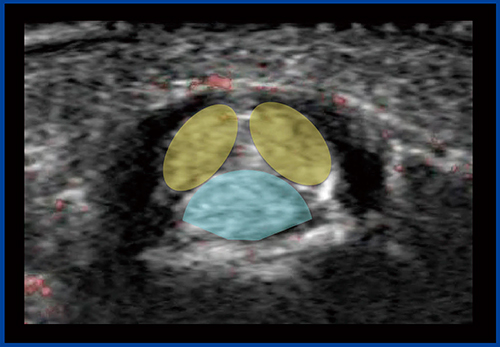

症例2は,Bモードにて中足骨と基節骨の関節の腫れと,関節液の貯留が確認され,一部に初期の骨びらんが疑われた(図5)。カラードプラ(図6)では,滑膜には豊富な血流が見られるが,骨びらんが疑われる部位にはほとんど血流が認められなかった。一方,SMI(図7)では,骨びらんの周囲から骨の中に流入する血流がわずかに認められた。

本症例は,未確定ではあるがリウマチが疑われる。通常,リウマチの診断はカラードプラを用いて行われるが,カラードプラでは滑膜の血流状態だけを見ているため,SMIを加えることで,リウマチ発生初期から見られる骨びらんを早期に評価できるようになると期待される。

図7 症例2のSMI画像

骨びらん周囲から骨の中に流入する血流をわずかに認める。

図11は,指屈筋腱の腱鞘炎(ばね指)症例の短軸像で,腱の周囲の腱鞘(黒い部分)が腫れているのがわかる。腱は1本ではなく,深指屈筋腱と浅指屈筋腱が組み合った構造をしている。注射をしながらSMIで観察すると,腱鞘をはじめ,腱と腱の間にも薬液が入る様子が観察できる(図12)。確実な治療効果を得るために,SMIでの観察が有用であると言える。

図11 指屈筋腱腱鞘炎の短軸像

●浅指屈筋腱

●深指屈筋腱